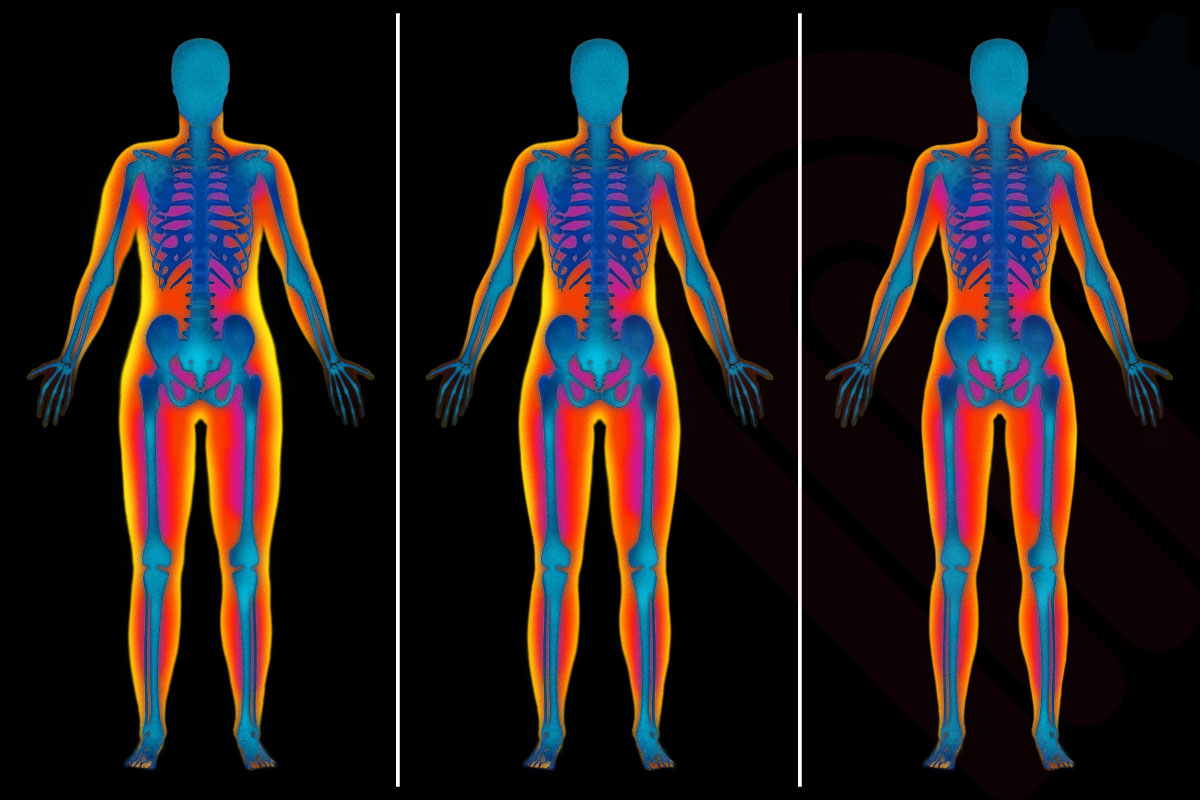

Hologic Horizon® DXA Sistemi, yalnızca kemik mineral yoğunluğu ölçümü yapmakla kalmaz, aynı zamanda tam vücut kompozisyon analizi sunar. Bu analiz, yağ kütlesi, yağsız doku kütlesi ve kemik mineral içeriğini bölgesel olarak ayrı ayrı ölçerek detaylı bir vücut profili oluşturur. Özellikle obezite, sarkopeni veya sporcu performans takibinde, klinisyenlere tedavi planlamasında kritik bilgiler sağlar.

Araştırmalar, DXA tabanlı vücut kompozisyon analizinin, biyoyelektrik impedans veya antropometrik yöntemlere göre daha yüksek doğruluk ve tekrarlanabilirlik sunduğunu göstermektedir*. Böylece hastaların kilo yönetimi, kas kütlesi korunumu ve metabolik sağlık takibi daha güvenilir bir şekilde yapılabilir.

Hologic Horizon® DXA sistemlerinde bulunan Athena™ yazılımı, hastaların yağ, kas ve kemik kütlesini bölgesel ve bütün vücut düzeyinde ayrıntılı olarak analiz eder. Özellikle obezite yönetimi, sarkopeni takibi ve sporcu performans değerlendirmelerinde yüksek doğruluk sağlar.

Athena™ yazılımı, sağ–sol taraf asimetrilerini, visseral yağ miktarını ve kas kütlesi dağılımını milimetresel hassasiyetle raporlar. Klinik çalışmalarda, DXA bazlı vücut kompozisyon ölçümlerinin %98’e varan tekrarlanabilirlik oranısunduğu gösterilmiştir*, bu da uzun dönemli takiplerde güvenilirliği artırır. Ayrıca, ölçüm sonuçları grafik ve renk kodlarıyla sunularak hem klinisyen hem de hasta açısından anlaşılır bir görsel geri bildirim sağlar.